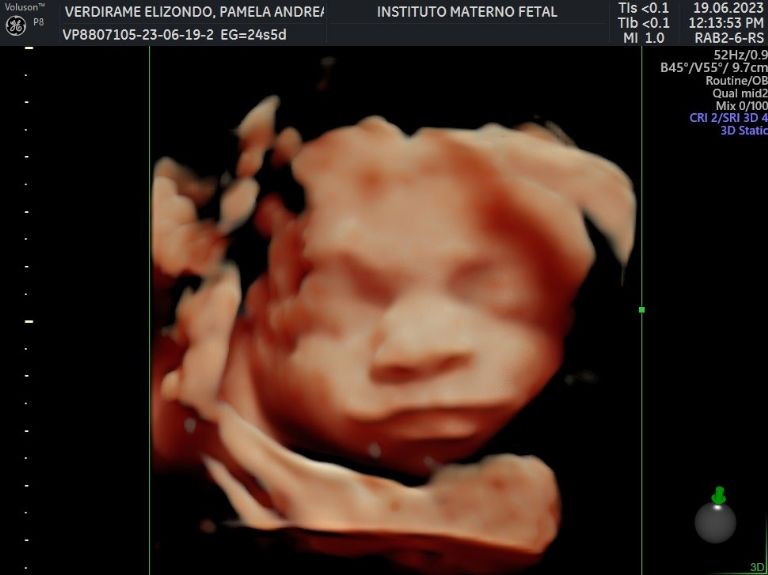

Hace unas horas, la pareja de atletas enterneció la red ya que a través de su cuenta oficial de Instagram, Pame mostró algunas imágenes de su reciente ultrasonido en el que ya se puede apreciar que el bebé ya se encuentra perfectamente formado e incluso se distinguen algunos de sus rasgos, por lo que hubo quienes trataron de buscarle parecido y fue tal el furor que causaron que superaron las 27 mil reacciones.

No saben la emoción que sentimos al ver a nuestro bebé. Nos llena de ilusión inmensa e inmensa felicidad su llegada. Inexplicable el amor que sentimos por este pedacito de cielo que llegó a multiplicar nuestro amor", escribió Verdirame.

Actualmente, Pame tiene 25 semanas de gestación, de tal forma que ya llevaba más de la mitad del proceso. De acuerdo a lo que ha compartido, el bebé podría nacer a principios de octubre, así que falta poco para que lo puedan tener entre sus brazos, mientras tanto se encuentran comprándole algunas cositas y preparan la decoración de su habitación, pues quieren que todo se encuentre perfecto para recibir a su pequeño.